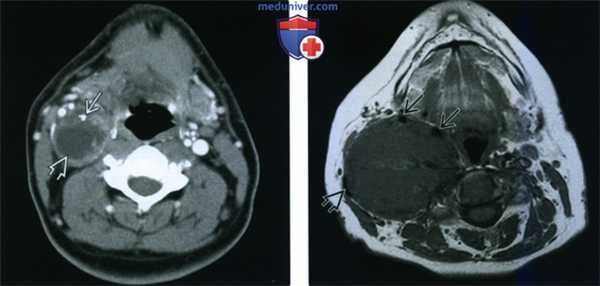

(Слева) КТ с КУ, аксиальная проекция. Образование овальной формы в заднемедиальном отделе сонного пространства. Обратите внимание, что сонная артерия находится на передней поверхности опухоли, а внутренняя яремная вена - на латеральной. Незначительное накопление контраста не очень характерно для шванном, в данном случае вид опухоли напоминает нейрофиброму.

(Справа) MPT Т2ВИ, аксиальная проекция. Округлое образование с неоднородным сигналом, которое смещает общую сонную артерию кпереди. Внутренняя яремная вена смещена вместе с артерией. При сдавливании яремной вены ее идентификация может быть затруднена.

(Слева) МРТ Т1ВИ FS с КУ, аксиальная проекция. В задних отделах подподъязычного сонного пространства расположено образование округлой формы. Шваннома симпатического ствола смещает и сонную артерию, и внутреннюю яремную вену кпереди. Одновременное смещение обоих сосудов сонного пространства весьма характерно для шванномы симпатического ствола.

(Справа) МРТ Т1ВИ FS c КУ, коронарная проекция. Шваннома симпатического ствола, расположенная в сонном пространстве. Опухоль неравномерно накапливает контрастное вещество. Участки кистозного перерождения в крупных шванномах встречаются достаточно часто.